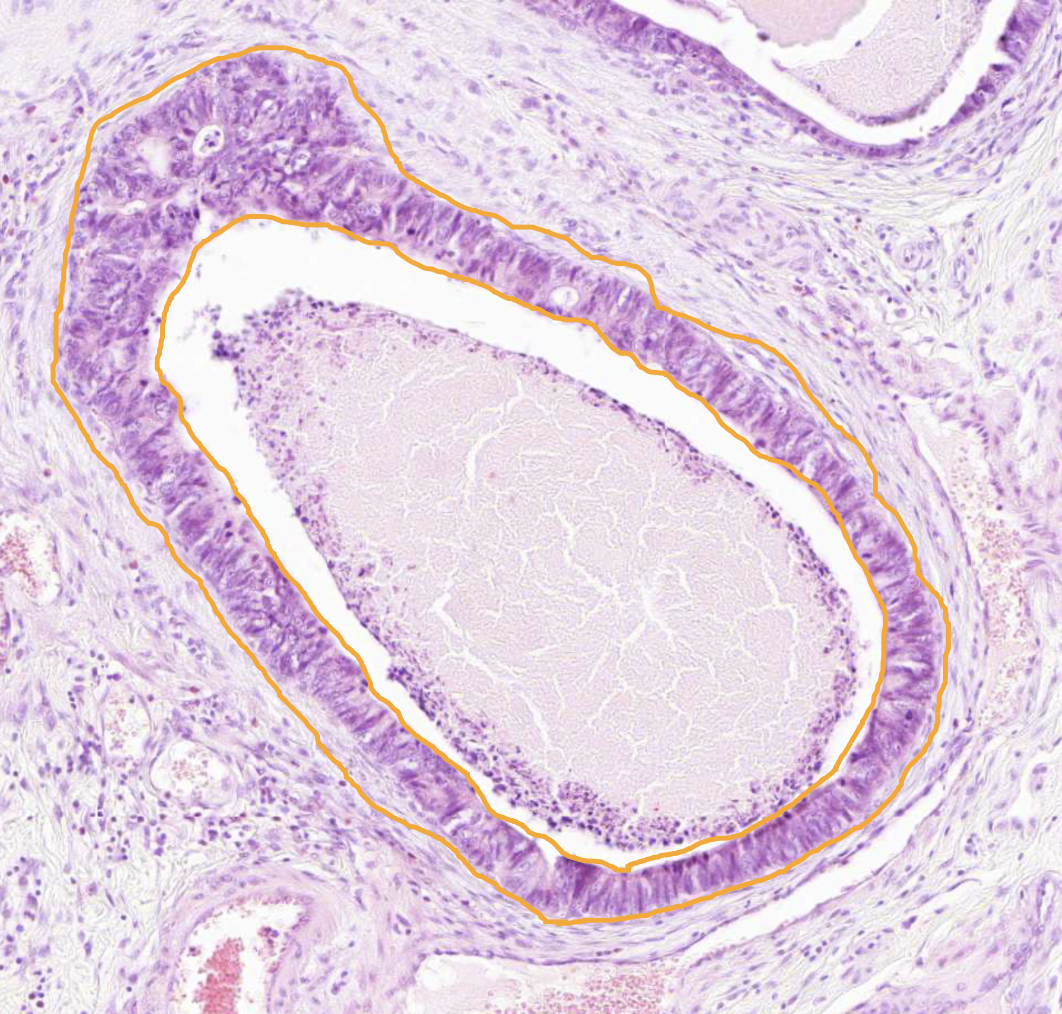

Normal colon - Lympho-glandular complex

Normal numbers of immune cells (mainly lymphocytes)

Well differentiated colon adenocarcinoma - Tumour cells

Nuclei on different levels (not in a row at the bottom of the cells as in normal crypts)

Well differentiated colon adenocarcinoma - Cylindrical epithelial cells of cancer glands

Irregular structure

Sometimes form several layers (pseudo stratified) due to compression

Densely packed

Polymorphic

Varied sizes and configurations

Relatively large nuclei and hyperchromatic

The mucin level in the cytoplasm is severely reduced compared to normal

Mitosis is frequent

Prominent nuceolus

Not all nuclei is not at the bottom of the cell as they are normally - Nuclei are not arranged in a straight line